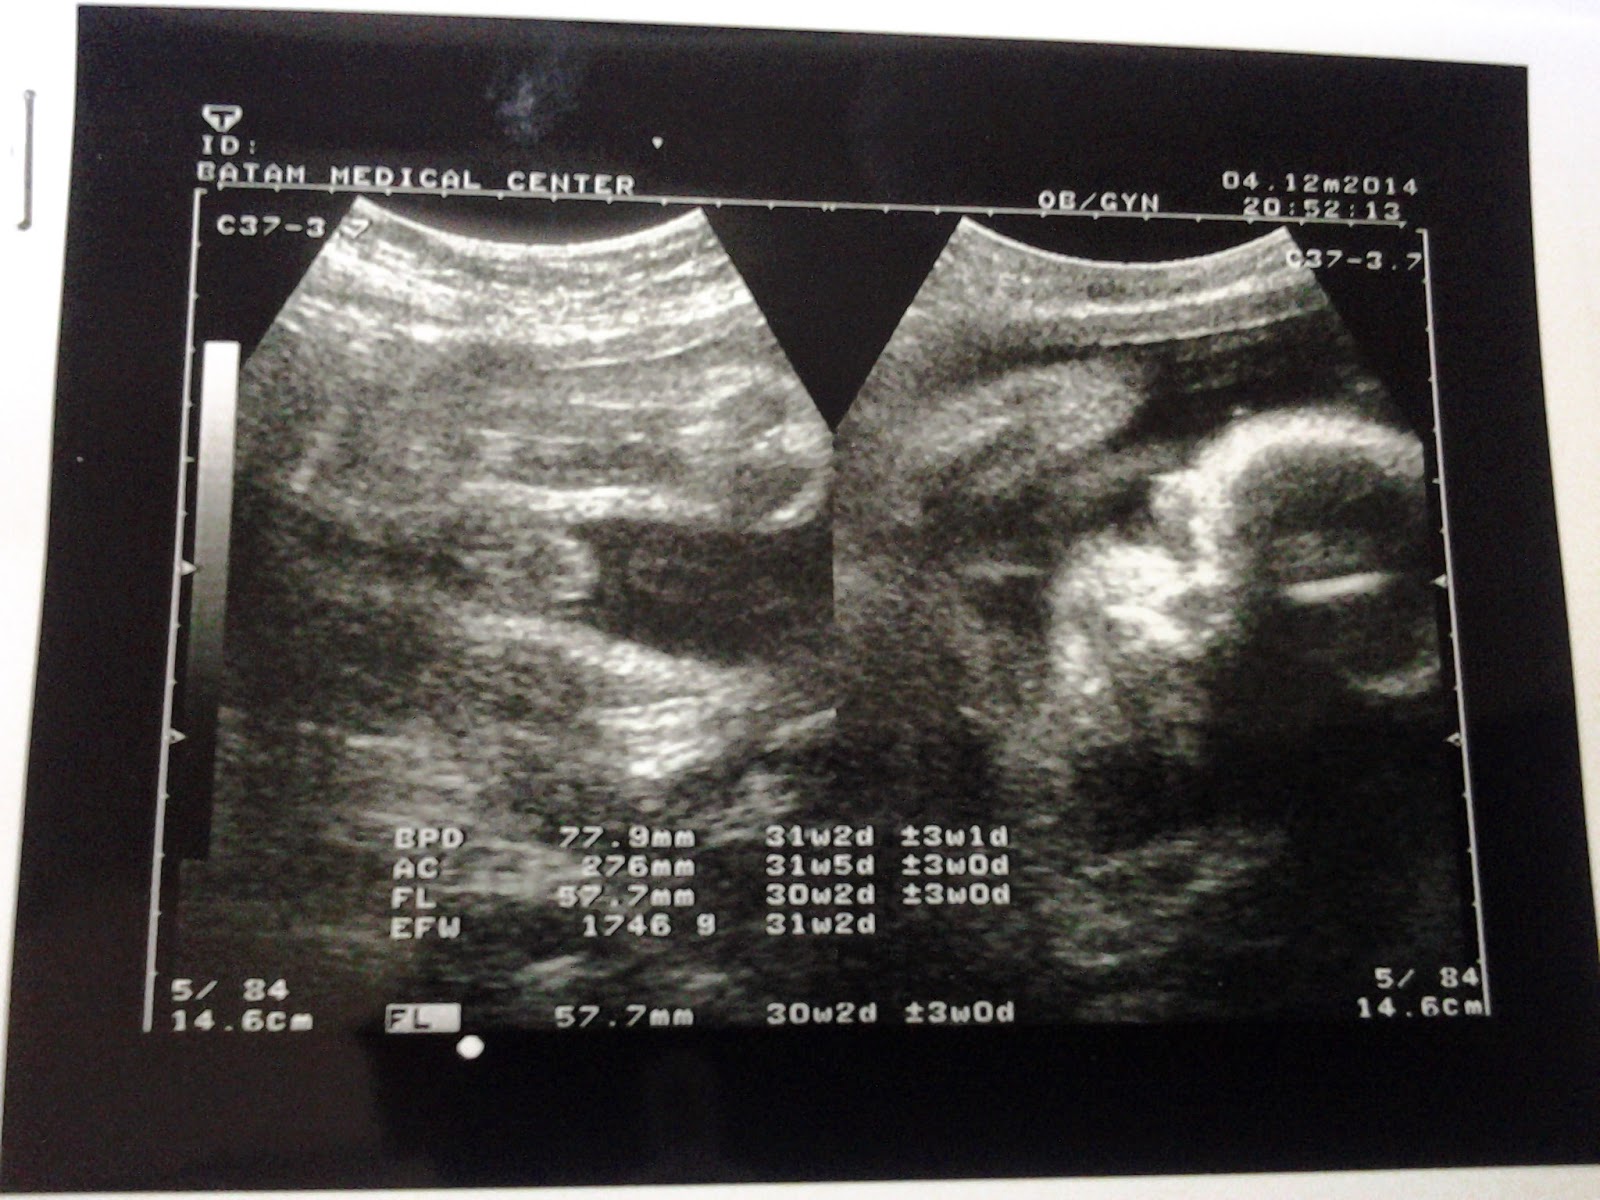

Ini hasil USG awal desember lalu.

Posisi udah bagus, kepala udah dibawah

Biparietal diameter 77.9 mm

Estimation Fetal Weight 1746 gram

Gestational Age 31w5d